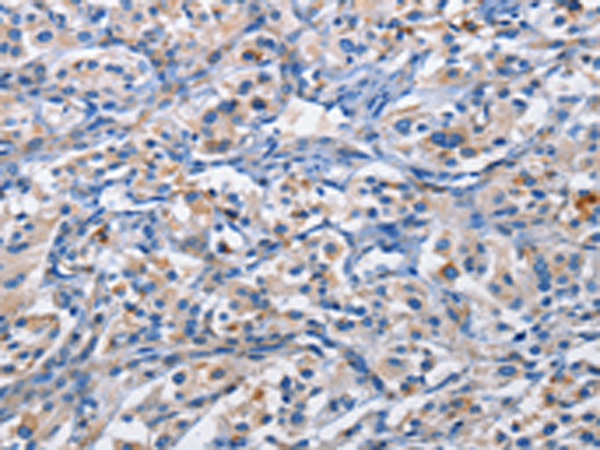

分类: 科研抗体货号: P07973别名: PIM应用: IHC反应种属: Human, Mouse, Rat